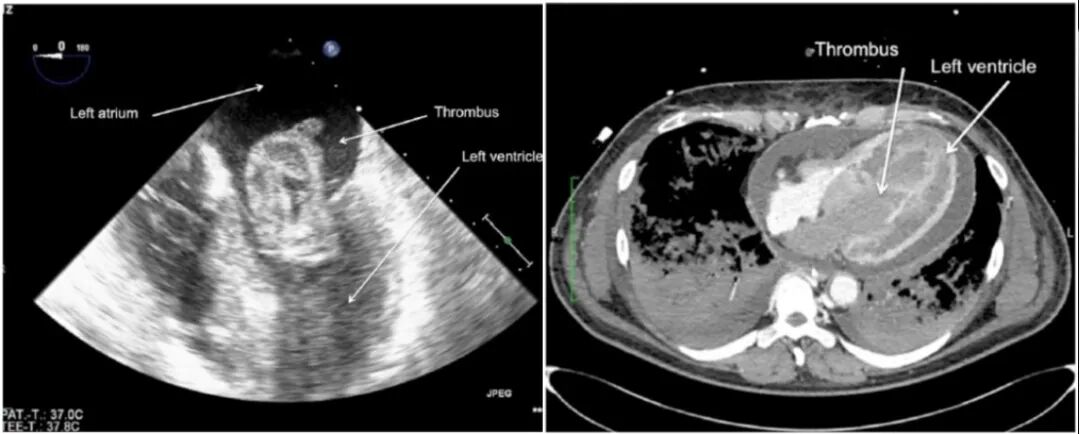

• 心内血栓形成

V-A ECMO患者可能出现心腔血栓。如果患者心功能极差而流量较高,可能导致主动脉瓣难以打开,出现明显的心腔内淤血,此时血流瘀滞易导致心腔内血栓,这是导致患者死亡的独立危险因素。患者心功能极差时,心腔内血液为涡流,血流速较慢,在超声方面可能表现为云雾样低回声,此时不一定意味着血栓形成,有时需要造影证实。

图片